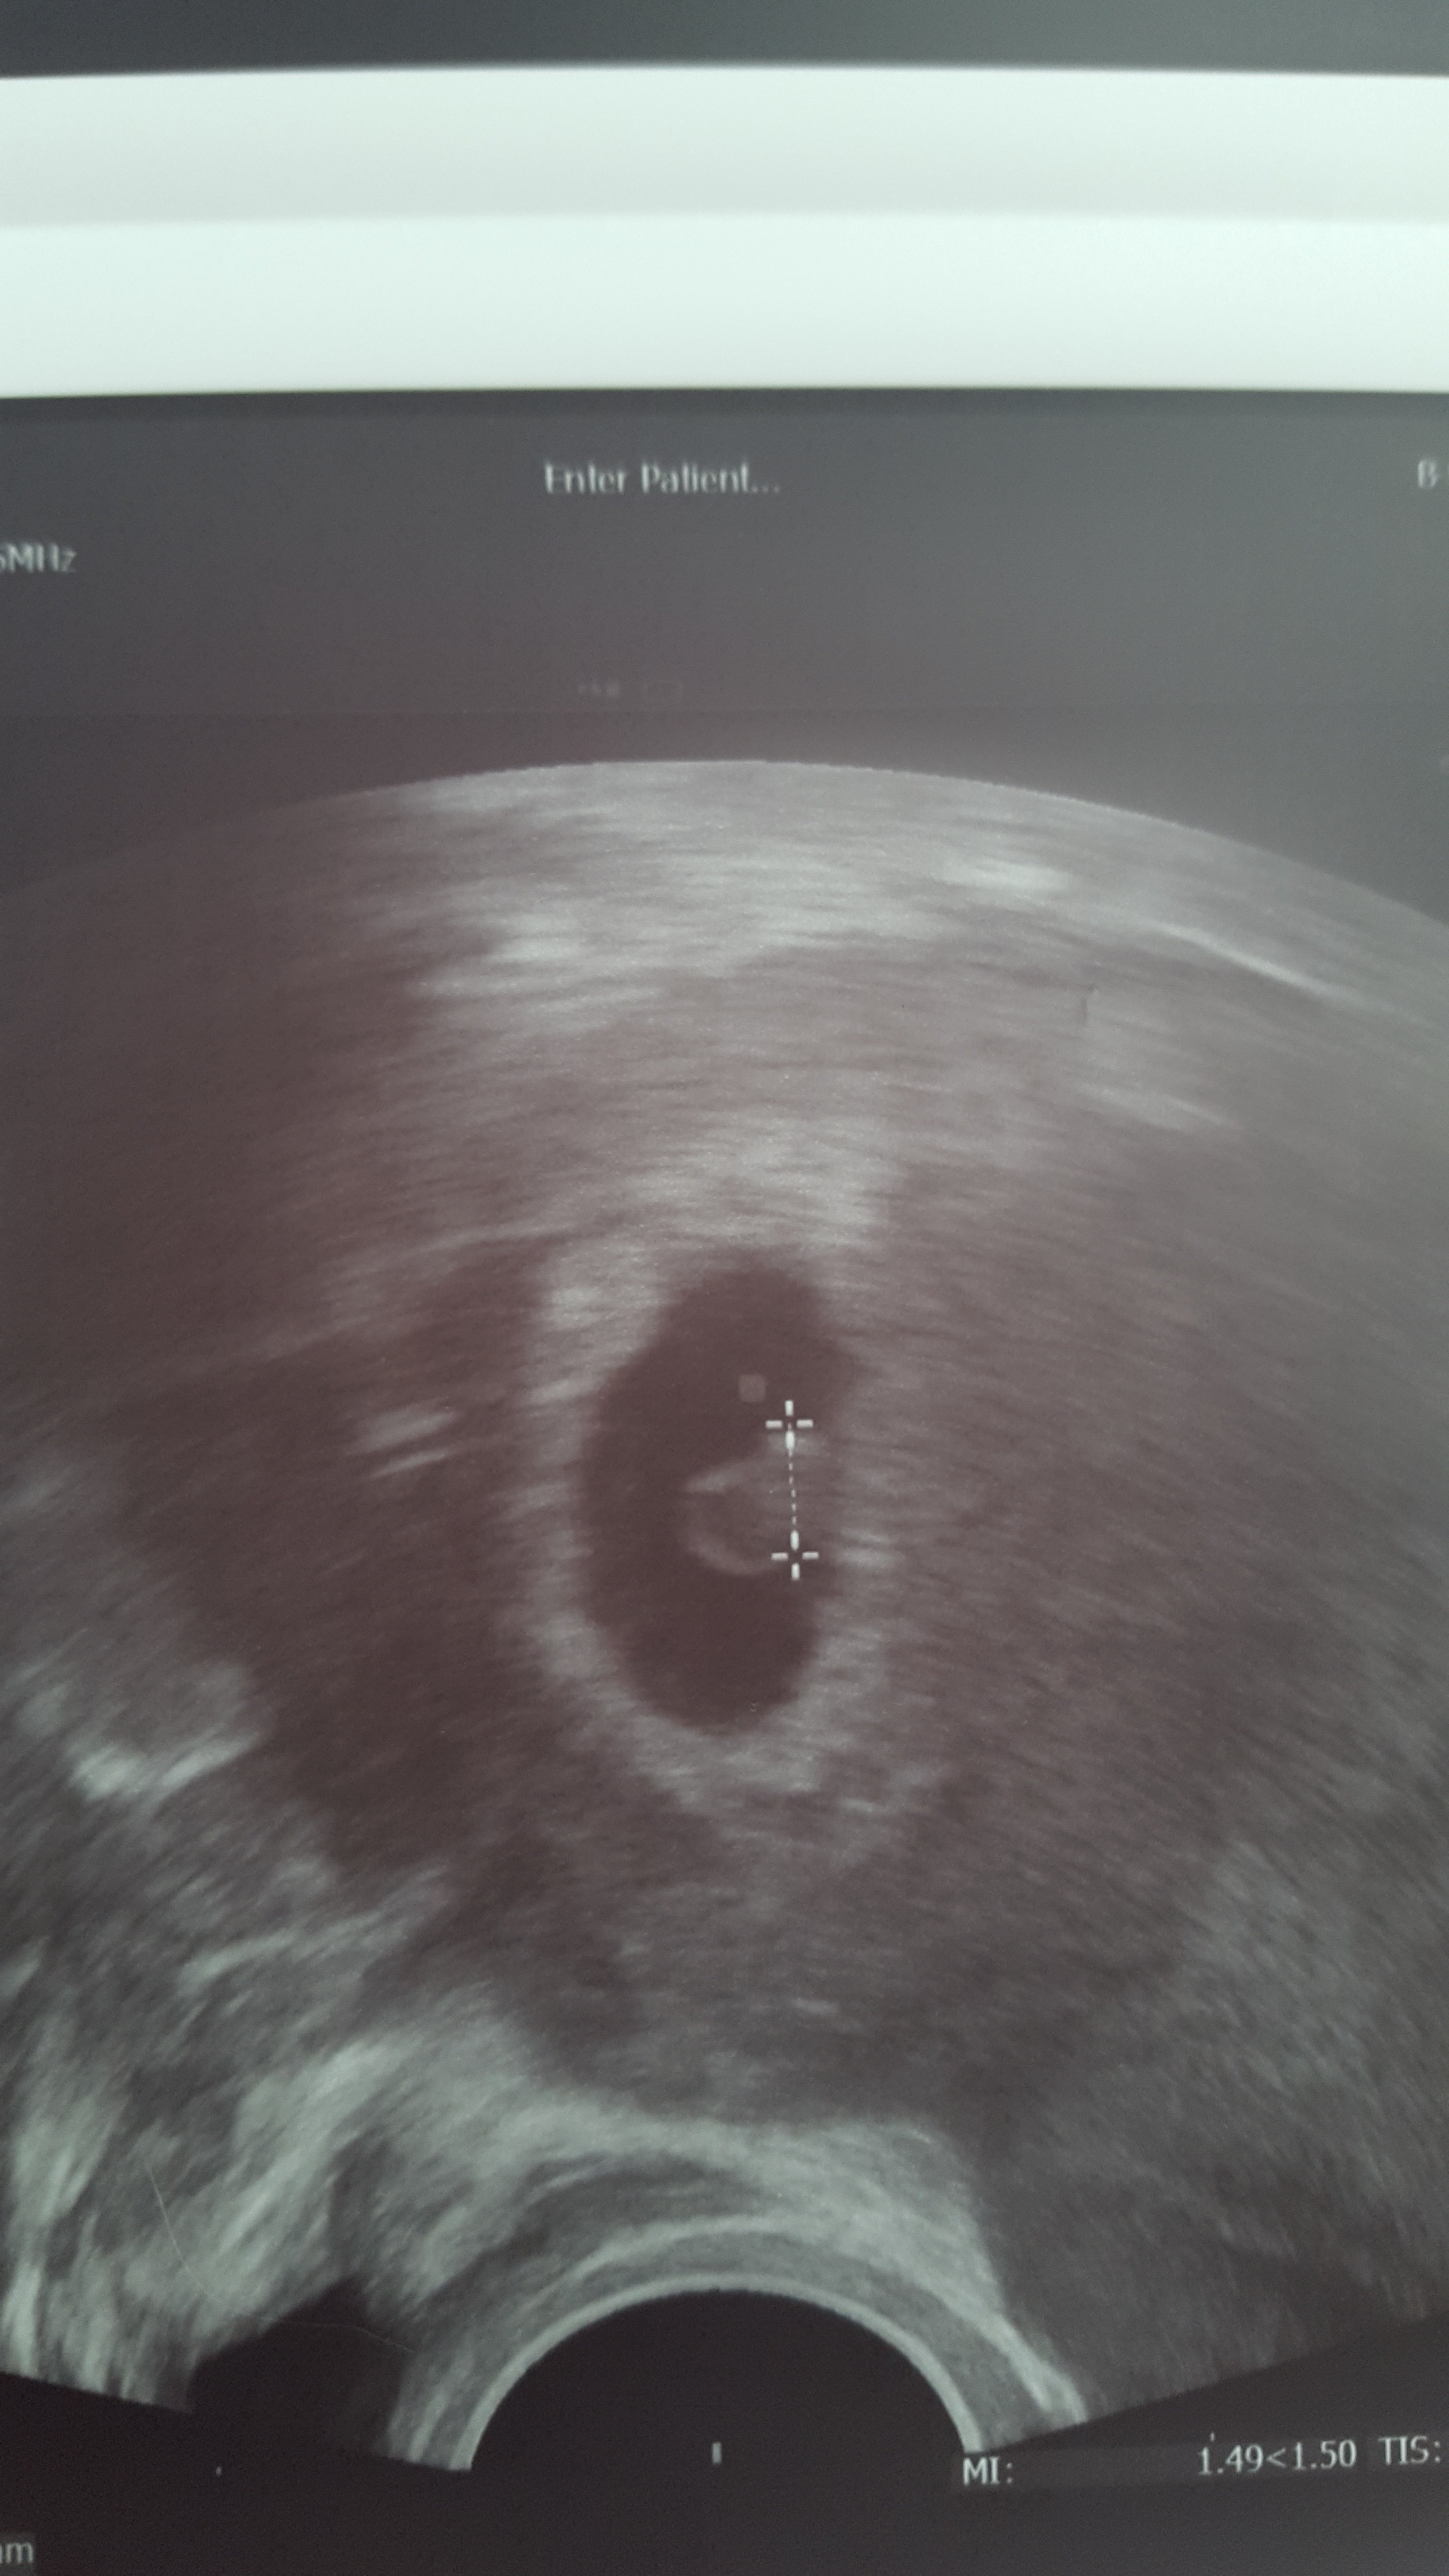

Moja fasolka z dzisiaj. 5mm i serduszko bije. Troche mi lepiej ale licze na większy spokój psychiczny po badaniach prenatalnych.

Załączniki

• 20200226_101058.jpg

20200226_101058.jpg

1,3 MB · Wyświetleń: 99